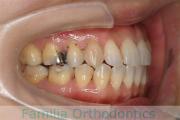

歯並びを治したいということで来院されました。下あごがやや右側に偏位して後退している、上顎前突(出っ歯)でした。上下左右から小臼歯を抜歯して、歯科矯正用アンカースクリューを併用したマルチブラケット法にて治療を行いました。約2年、24回の来院をしていただきました。

下顎の後退はいびきなどの上部気道の障害が出やすいと考えられます。